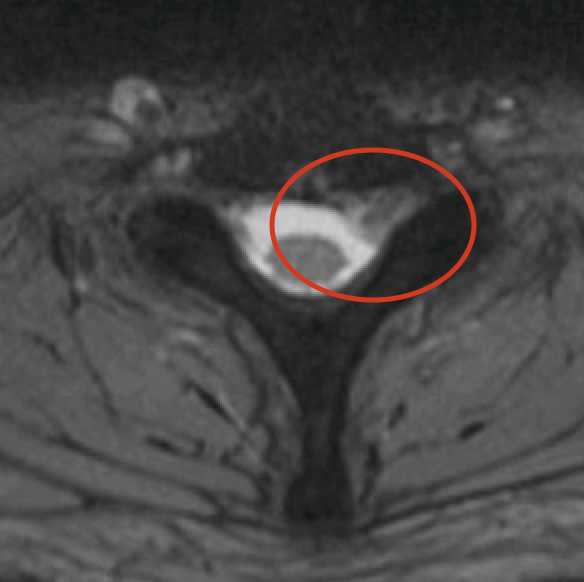

Het ideale onderzoek is een NMR (=MRI). Het levert ons de beste beelden en gebruikt geen nadelige X-stralen. Soms wordt ook een CT scan van de nek gevraagd.